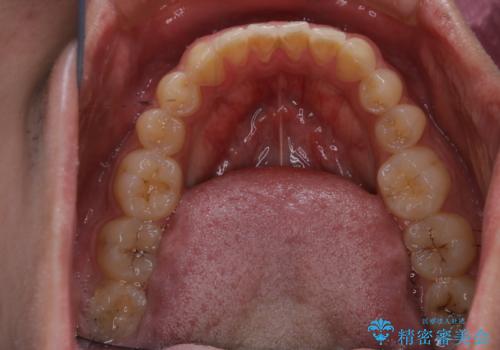

矯正治療中は虫歯や歯周病リスクが高くなることがあります。

インビザライン矯正治療はマウスピースで1日20時間以上歯列全体を覆っているため、歯石や汚れなどが付着したままだと、フィットが悪くなったり、口臭が強く出たりする原因につながることもあります。

今後、矯正を考えている場合は、まず現状の口腔内をチェックし、虫歯や歯周病などを早期に発見し進行を防ぐことが大切です。

表参道しらゆり歯科 DH西澤